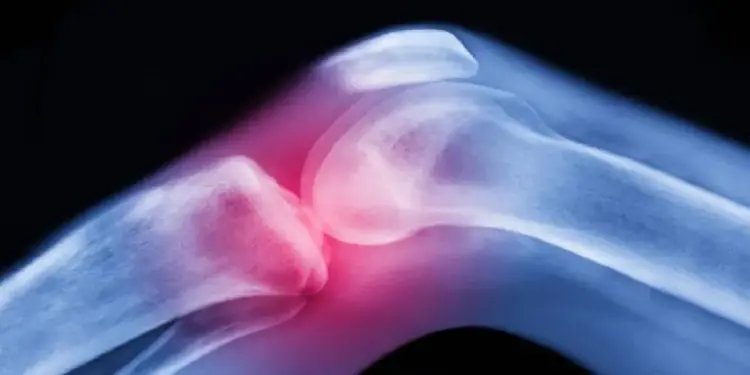

Más de 200 millones de personas en todo el mundo padecen osteoporosis, un grave debilitamiento de los huesos que puede causar fracturas frecuentes.

Las mujeres corren un riesgo especialmente alto de osteoporosis después de la menopausia debido a la disminución de los niveles de la hormona sexual estrógeno, que normalmente favorece la formación de hueso.

Pero aunque los niveles de estrógeno también son bajos durante la lactancia, la osteoporosis y las fracturas óseas son mucho más raras en este periodo, lo que sugería que había otros factores que promueven el crecimiento óseo.